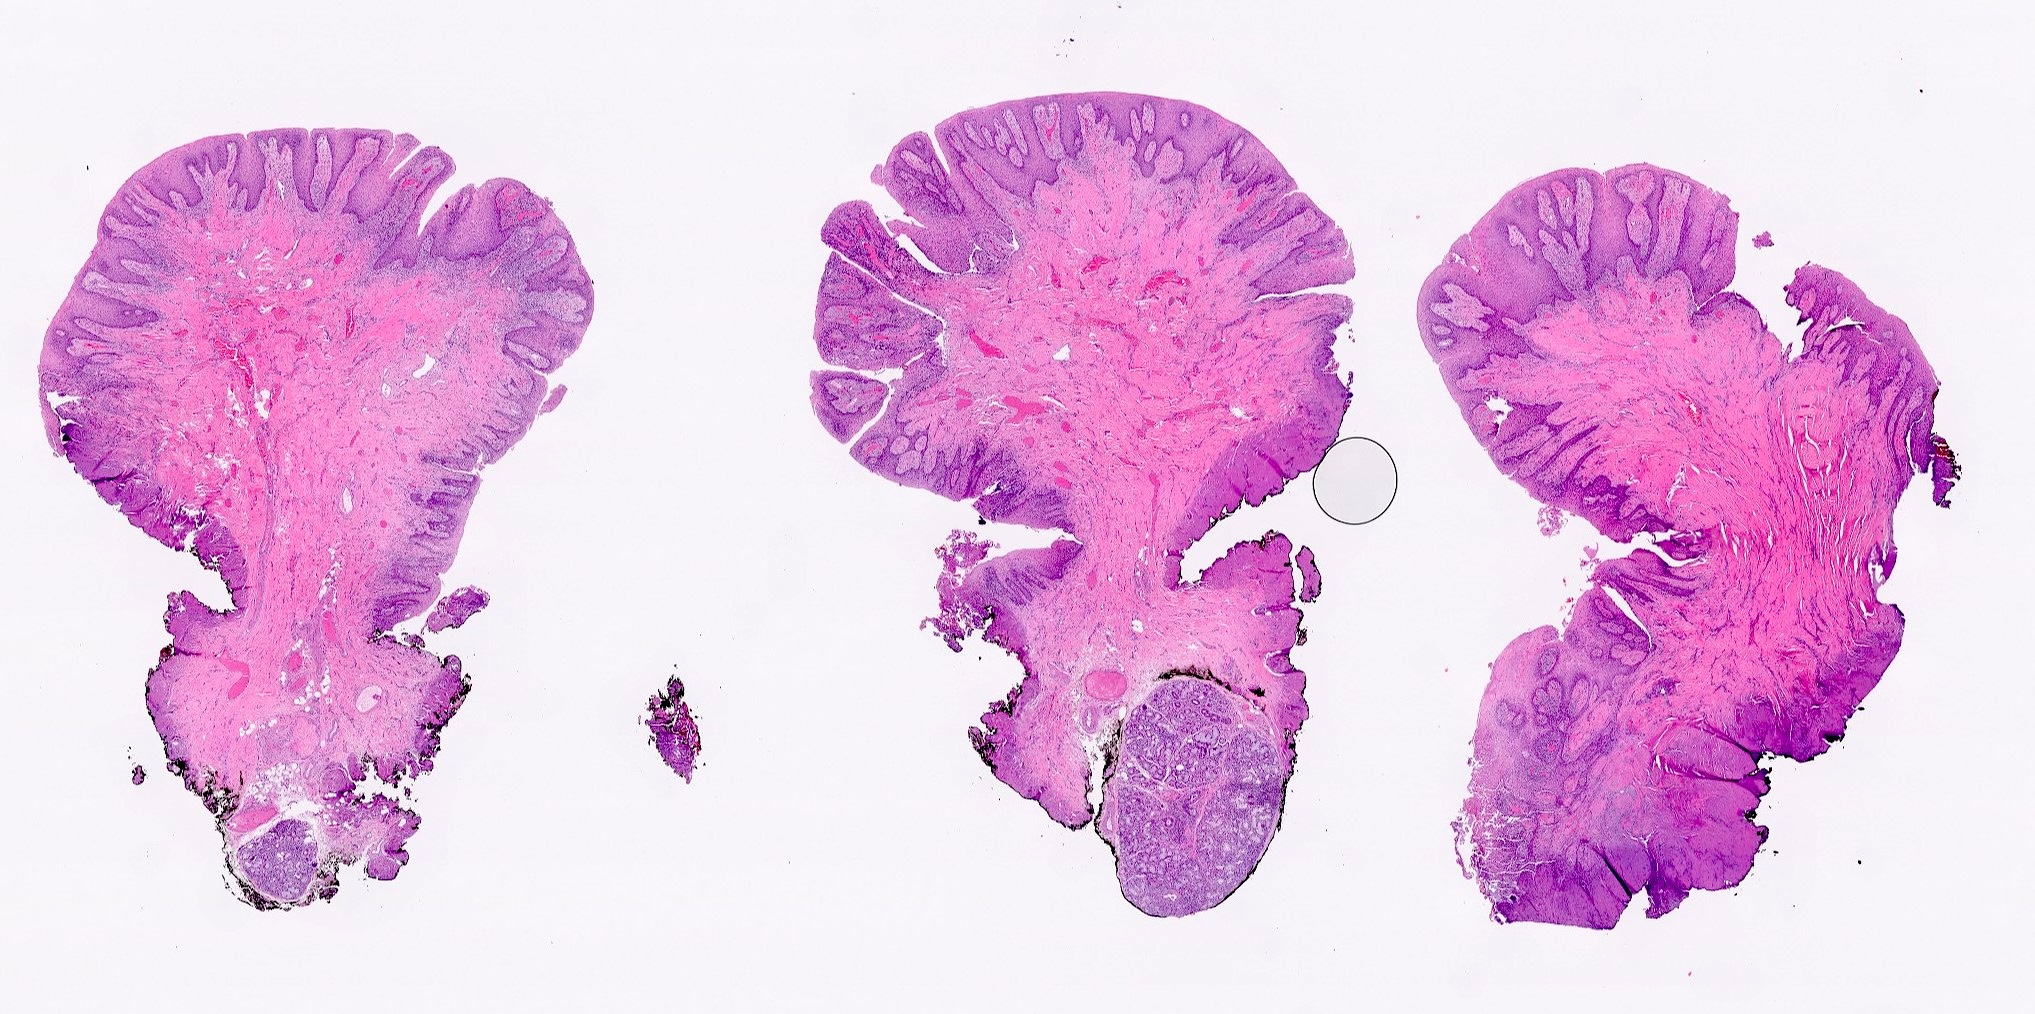

- Hyperplastic keratinized squamous mucosa overlying dense nodular connective tissue and variable inflammatory infiltrate (Acta Histochem 2016;118:451, Head Neck Pathol 2019;13:103)

- Underlying connective tissue is variably collagenized with scant bland spindled fibroblasts (Head Neck Pathol 2019;13:103)

- Pseudoepitheliomatous hyperplasia or secondary candidal colonization may be present

C. Inflammatory fibrous hyperplasia. The image shows squamous mucosa overlying a dense collagenous proliferation with focal chronic inflammation. Answer A is incorrect because amyloidosis is an accumulation of an acellular eosinophilic amorphous material in the submucosa. Answer B is incorrect because giant cell fibroma is not related to a history of chronic irritation. Morphologically the submucosa contains numerous stellate fibroblasts that can be multinucleated. Answer D is incorrect because solitary fibrous tumor is a cellular and vascular neoplastic proliferation; it does not have abundant reactive collagen.